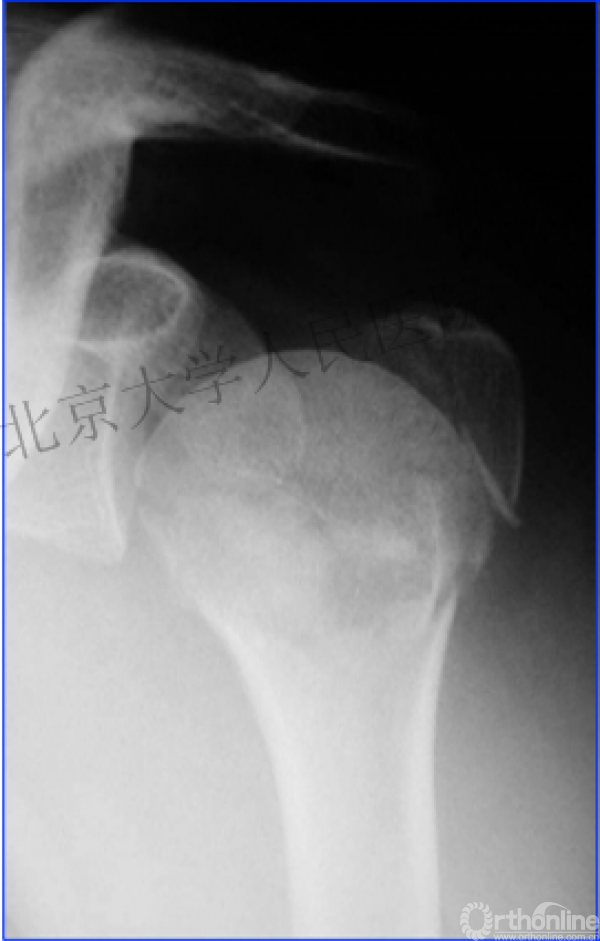

另一个留有遗憾的病例,您的选择?PHN?

两部分骨折的生物力学

作为髓内固定,抗轴向压力较偏心固定的钢板强。